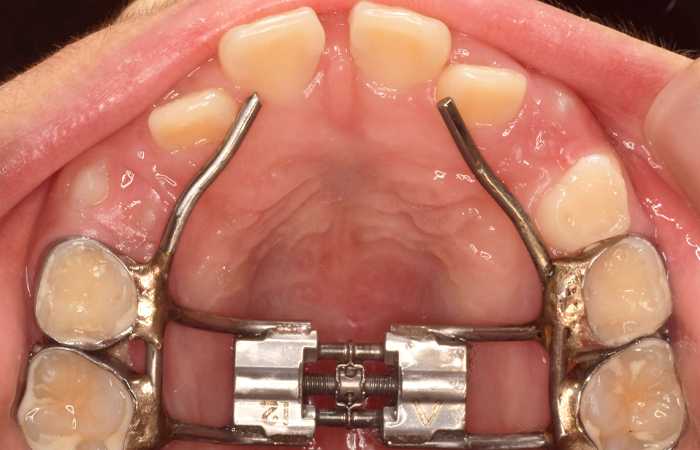

いずれも上顎の成長が不十分であることが原因であったため、顎顔面矯正とフェイシャルマスクを併用して治療しています。

特殊な装置を使って、歯だけでなく顎の骨全体を正しい位置に導いていく治療法です。 顎の骨を拡大し、正しく成長させることで、歯を自然と正しく並べることができます。

特殊な装置を使って、歯だけでなく顎の骨全体を正しい位置に導いていきます

たけだ歯科で行う顎顔面矯正は少しずつ上顎の骨を動かす矯正です。